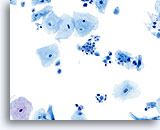

Postpartum Changes

During the postpartum period, or if breast feeding, a hormonal pattern of low squamous maturation predominates. Parabasal cells are abundant, usually presenting singly. Glycogen may also be present. A background of inflammatory cells and reactive changes is often present and may require additional scrutiny. Adherence to strict cytologic criteria (the lack of an increased N/C ratio, abnormal chromatin and irregular nuclear membranes) should preclude an over-diagnosis of cytologic atypia.

Postpartum

High power view of parabasal cells during postpartum. Note presence of glycogen and low N/C ratio. 60X